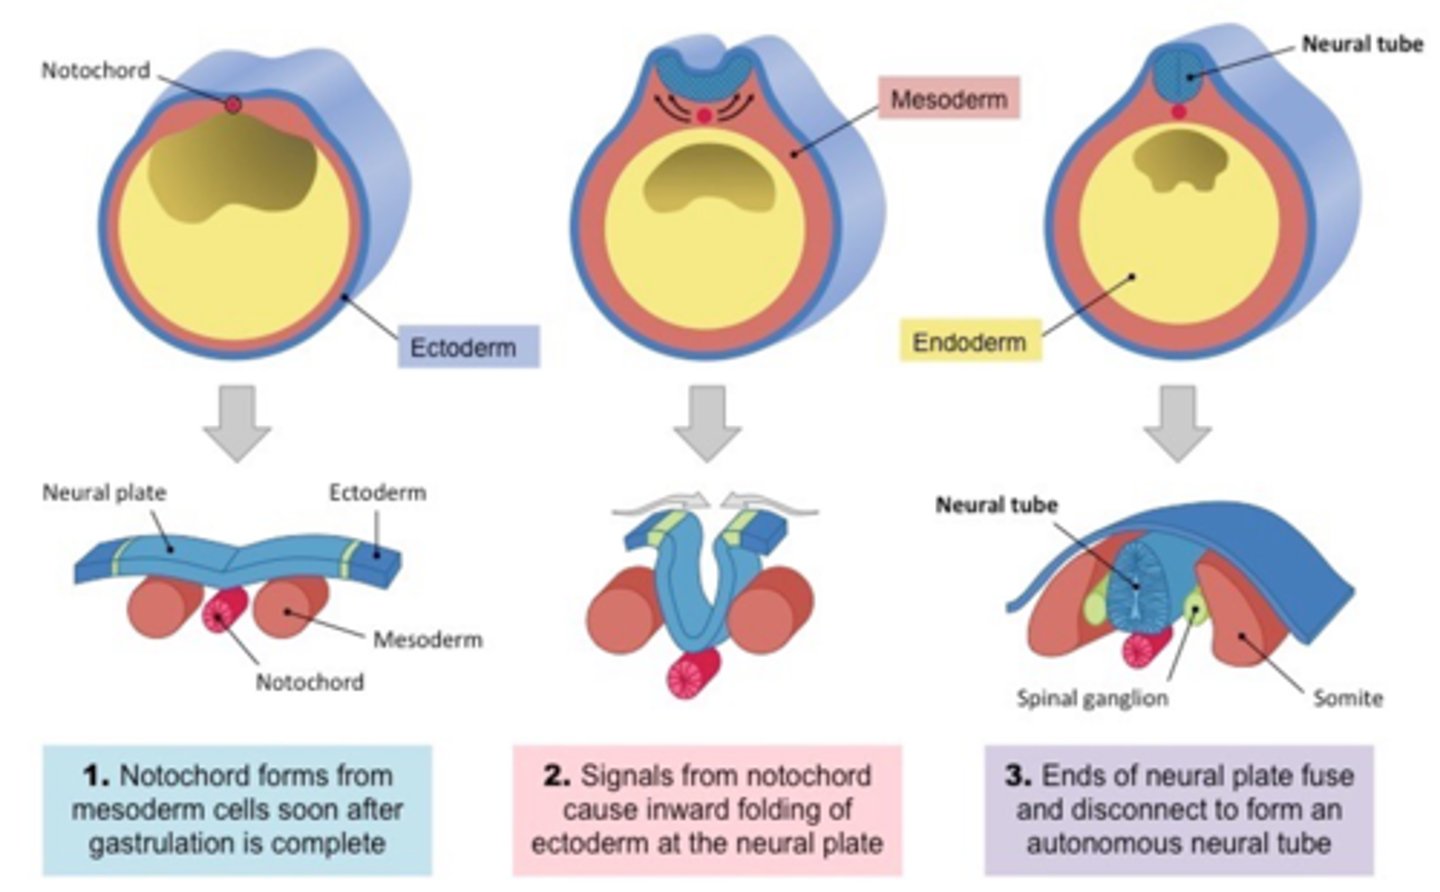

what term refers to the process where the neural plate forms the neural tube?

neurulation

the CNS appears as a plate of thickened (endoderm/mesoderm/ectoderm) and forms the neural ________ induced by the ___________. the edges of the structure will then elevate and form the neural __________. the edges eventually approach the midline and fuse to form the neural _________.

ectoderm during the 3rd week

plate

notochord (thickening of mesoderm)

folds

tube

what are the cells that appear along the edge of the neural plate as it elevates?

neural crest cells

what are ganglia, meninges, and Schwann cells derived from?

these arise from the neural crest cells

the fusion of the neural folds begins in the __________ region then proceeds ___________ and __________ to form the neural ________

cervical, cranially, caudally, tube